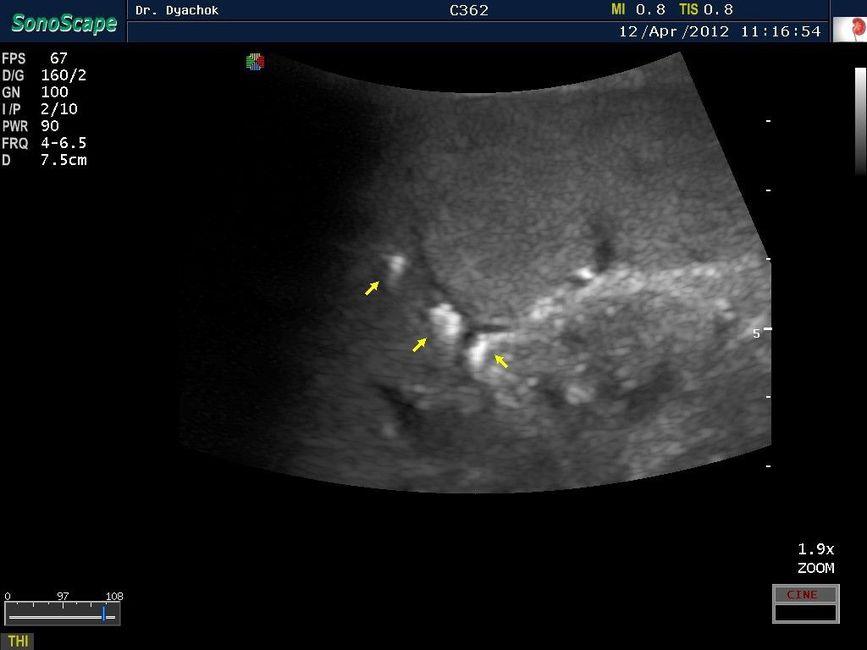

• Специализированный режим улучшенной визуализации биопсийной иглы

• Поддержка работы с ультразвуковыми контрастными веществами